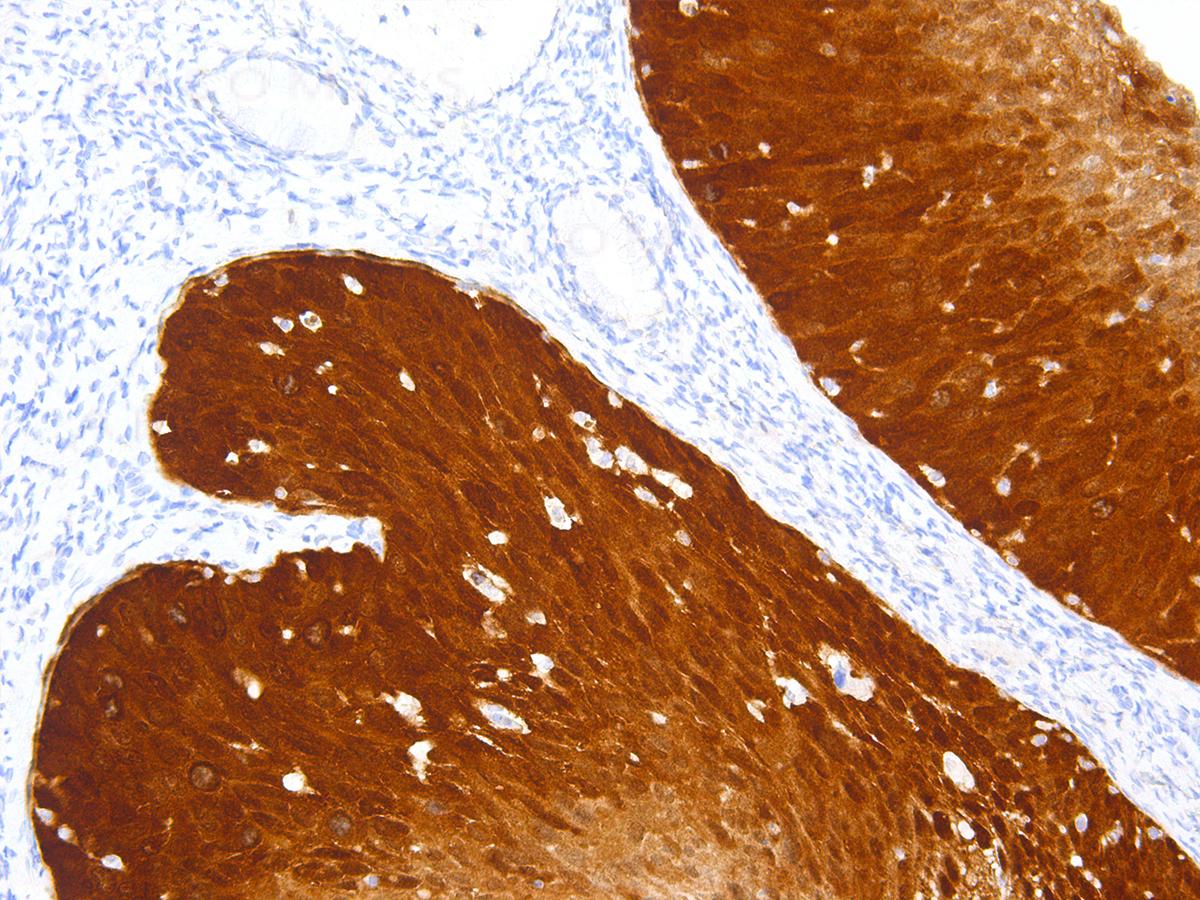

Anti-p16 Monoclonal Antibody (Clone:IHC116)

Figure 1: Immunohistochemical analysis of p16INK4A (IHC116) on Cervical Cancer

The p16 (p16INK4A) protein is a cyclin-dependent kinase inhibitor that plays an important regulatory role in the cell cycle. By controlling the transition between the G1 and S phases through regulation of retinoblastoma protein, p16 decelerates cellular differentiation and therefore acts as a tumor suppressor, making it the key marker in several human cancers including head and neck cancer, perianal lesions, melanomas, gliomas, lymphomas, and some types of leukemia. p16 is also clinically indicated in carcinomas of the esophagus, pancreas, lung, biliary tract, liver, colon, and urinary bladder.